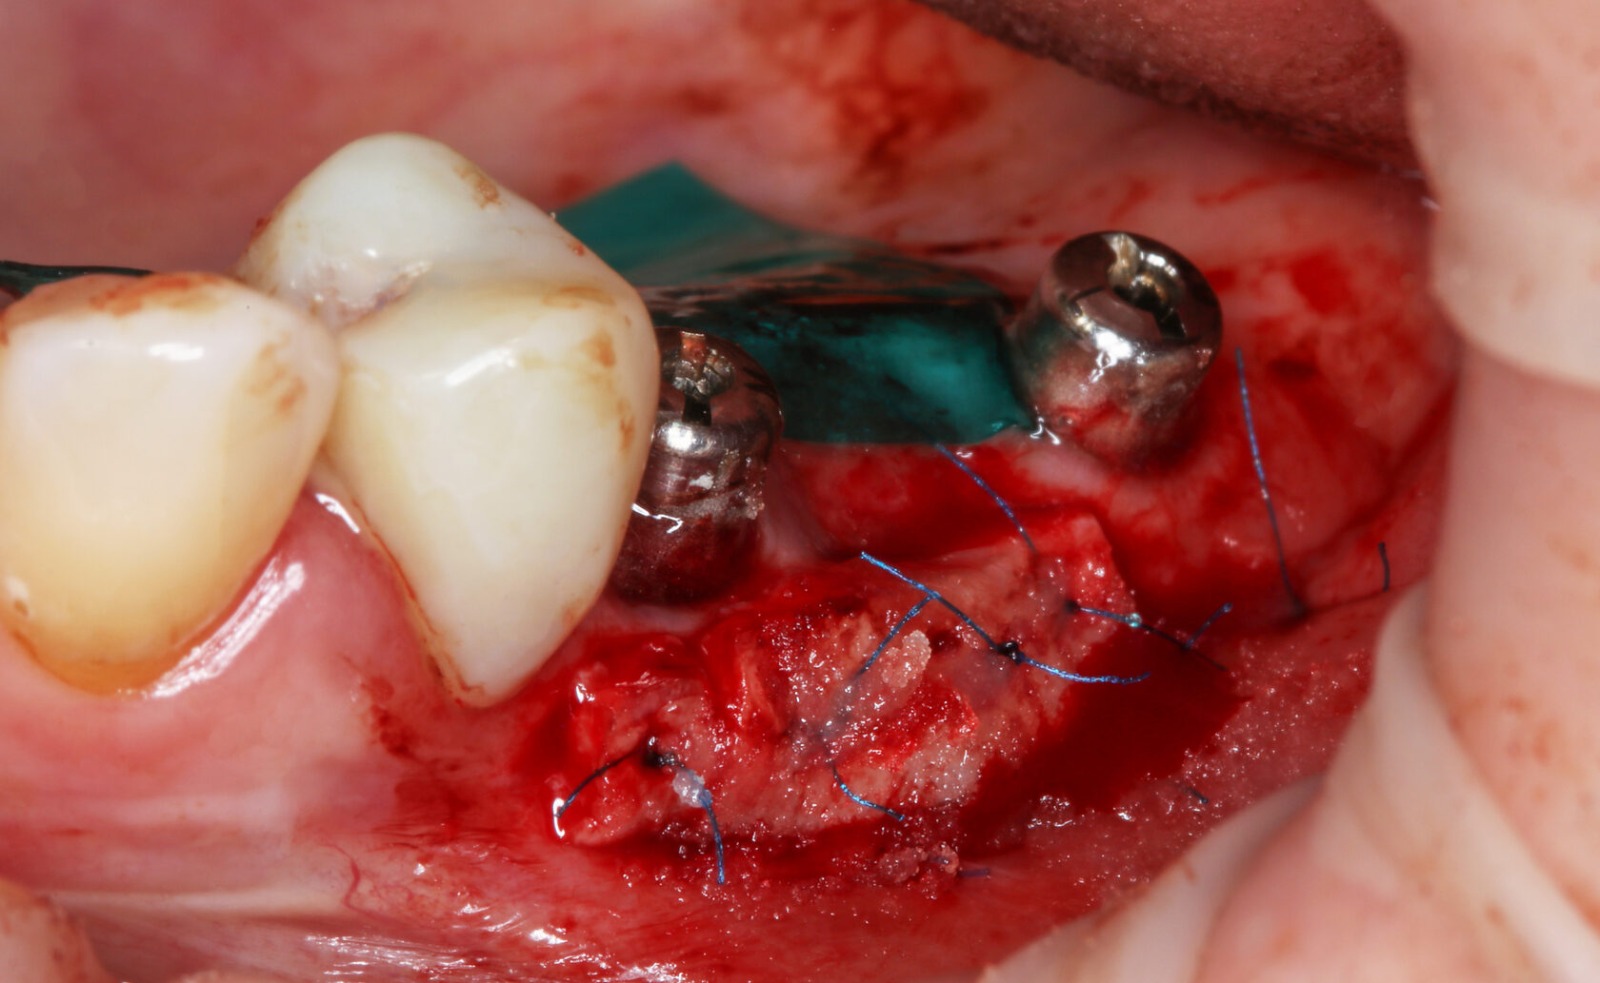

Фотографии учебного материала